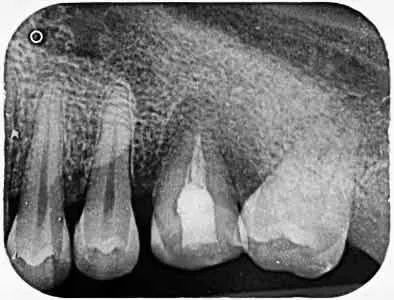

左下6牙选中合面洞,没内有食物残渣,去除残渣可见息肉,根尖片显示左下6牙髓腔底穿通,左下8牙阻生(比较遗憾当时我们用的胶片拍摄的片子,后胶片丢失)。

术后即刻拍片